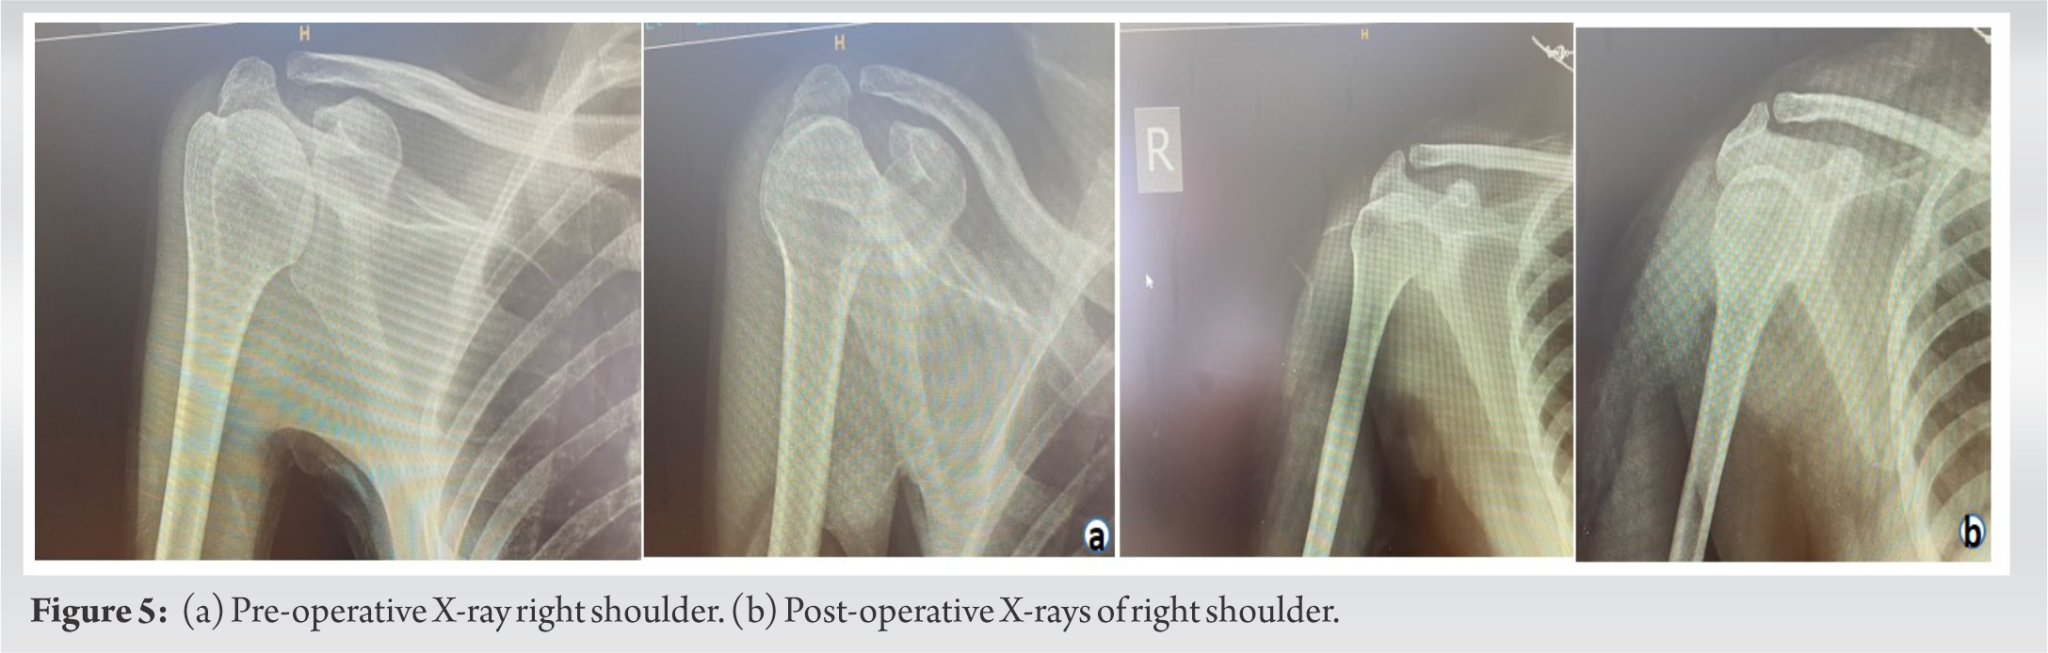

Anterior dislocation of the shoulder joint after arthroscopic pancapsular release for chronic Adhesive Capsulitis Case Report This review discusses the diagnosis. Adhesive capsulitis is a musculoskeletal condition that has a disabling capability. Operative treatment of idiopathic adhesive capsulitis is efficacious and safe for improving shoulder rom across treatment. Patients with adhesive capsulitis present with a gradual and progressive onset of pain and loss of active and passive shoulder motion in both. The purpose of this case. Adhesive Capsulitis Case Report.